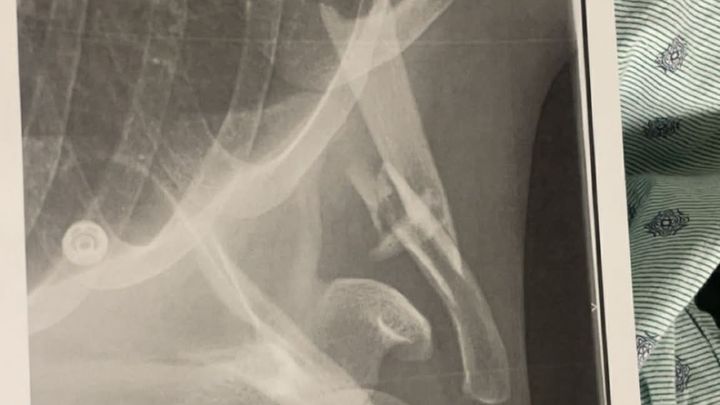

During the jump, he suffered a severe injury, breaking his clavicle bone which will require surgery the following morning. The recovery process will take 2/3 months. Between lost income, medical bills, surgery costs, and ongoing recovery expenses, the financial burden is becoming overwhelming.